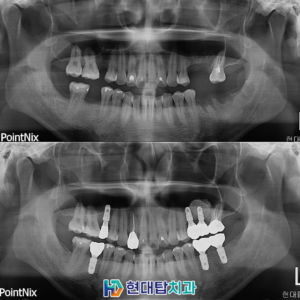

울산의식하진정임플란트 잠을 자듯 편안하게 받을 수 있는   안녕하세요, 많은 노하우와 임상경험을 가진 울산의식하진정임플란트 잘하는 현대탑입니다. ​ 오늘 보여드릴 증례는 하루만에 인레이, 발치 후 신경치료를 진행한 환자분을 보여드리도록 하겠습니다. ​ 우선 환자분의 치아 건강 상태를 확인 후 진료가 들어갔습니다. ​ 더보기…